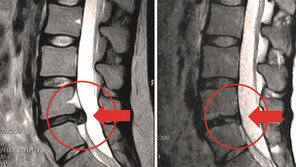

흔히 디스크는 50대 이상의 중장년층에게 나타나는 질병이라고 생각하기 쉽다. 그러나 통계청에 따르면 최근 20, 30대의 디스크 환자 비율이 크게 증가했으며, 10대의 발병률 또한 점차 높아지고 있다. 특히 20, 30대의 젊은 연령층에서는 목디스크가 높은 발병률을 보이고 있으며, 4…